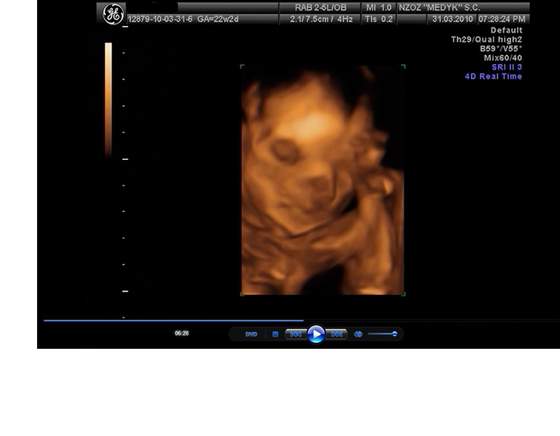

Pola juz po usg połowkowym. Jest zdrowiutka ma już 25 cm razem z nożkami i waży koło 350g. I jets strasznym wiertkiem. Załączam zdjątka

2. Pola kciukiem w buzi